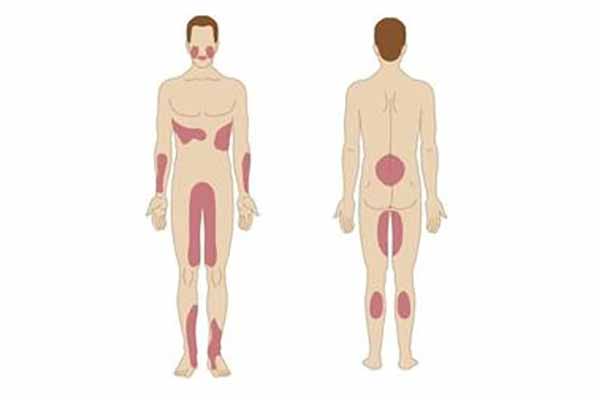

Фото Красного Плоского

Фото Красного Плоского 103 фото